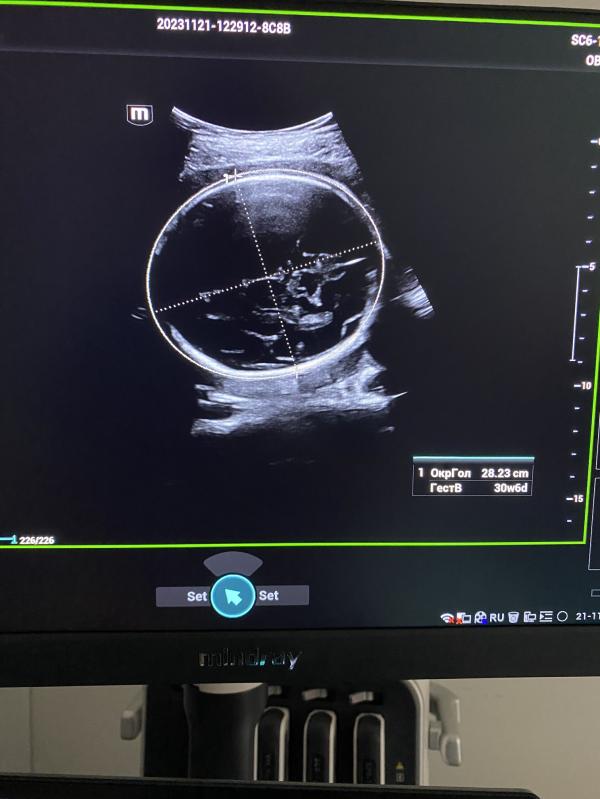

post image 2

27.11.2023 на приёме в МЦ Авиценна Гоголя 12 б второй проезд

На первом фото эндометриоидная киста до 6 см , в данном случае планируем беременность, так после операции есть риски снижения овариального резерва.